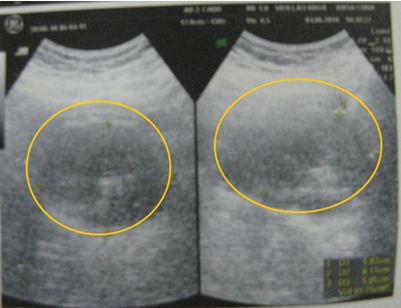

Kết quả siêu âm (đầu dò trực tràng): Tuyến tiền liệt to 86g, không đồng nhất có nhiều nốt vôi hoá, bờ không rõ, chèn ép niệu đạo tuyến tiền liệt, xâm lấn túi tinh trái. Như vậy chúng tôi đánh giá u nguyên phát là T3 (u xâm lấn qua vỏ bao tuyến) theo phân loại TNM của tổ chức Y tế thế giới.

Hình ảnh siêu âm (đầu dò trực tràng): tuyến tiền liệt (trong vòng tròn màu vàng) có âm không đồng nhất, nhiều nốt vôi hóa.